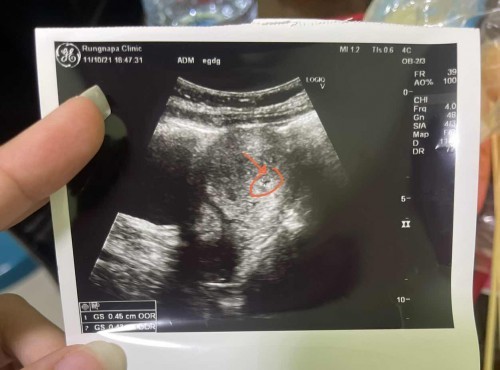

สวัสดีค่ะ ขอปรึกษาแม่ๆ ประจำเดือนขาด 6 วัน เลยตรวจสรุปขึ้น 2 ขีดทั้ง 3 อัน ไปซาวด์คุณหมอบอกว่า ยังซาวด์ไม่พบอะไร น่าจะท้องอ่อนเกินไป หมอบอก 3 สัปดาห์ แต่นับตามแอพ 5 สัปดาห์ค่ะ แต่คุณหมอบอกเหมือนจะมีจุดเล็กๆที่กำลังสร้าง #ที่วงกลมแดงๆไว้ และผนังมดลูกหนาแล้ว หมอแจ้งมาค่ะ และให้มาตรวจใหม่เดือนหน้า คำถามคือ 1. ผนังมดลูกหนาเเล้วเรามีสิทธิ์ท้องนอกมดลูกไหมค่ะ 2. เราต้องไปฝากท้องตอนกี่วีคค่ะ ถึงเจอถุงตั้งครรภ์และตัวน้อง *** ส่วนตัวท้องแรกเคยแท้งค่ะ ท้องแบบไม่รู้ตัวใช้ชีวิตทำงานหนักไม่ระวัง แท้งน้องหลังแท้งมีการติดเชื้ออุ้งเชิงการ รักษาจนหาย ก็บำรุงโฟลิคจนครบ2-3เดือน ก็มาติดท้องนี่ค่ะ กังวลมากค่ะ ไม่อยากผิดหวัง ***#ท้องแรกคะ #ใครมีประสบการณ์ #ขอบคุณสำหรับคำตอบค่ะ